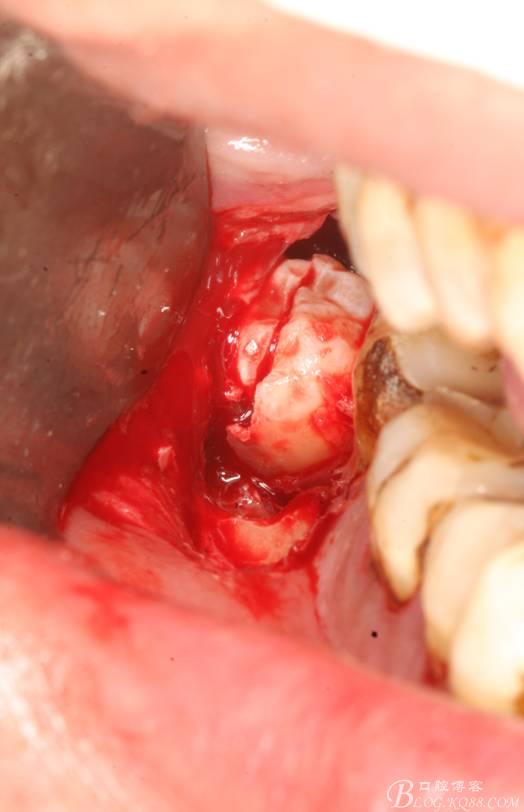

4. 縱分牙根和牙冠

5.取出牙根

6.橫斷牙冠